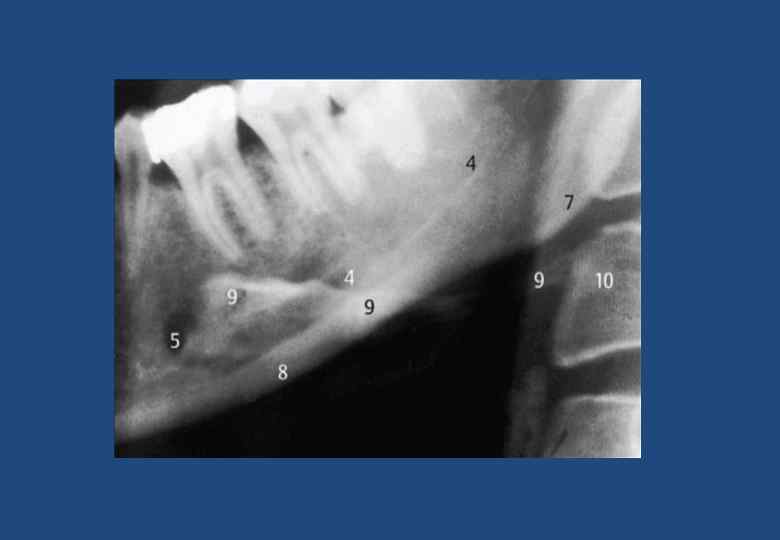

• • • • • • • 1. Верхнечелюстная пазуха границы 2. Горизонтальная пластинка небной кости и латеробазальная граница полости носа 3. Венечный отросток, наслаивающейся на крыловидный отросток клиновидной кости, бугор верхней челюсти и мягкие ткани небной занавески 4. Тело скуловой кости с безымянной линией 5. Безымянная линия (линия на височной поверхности скуловой кости) 6. Скуловая дуга 7. Височно-скуловой шов 8. Суставная ямка 9. Суставной бугорок 10. Мягкие ткани ушной раковины 11. Наружный слуховой проход 12. Мыщелковый отросток и головка нижней челюсти 13. Шиловидный отросток височной кости 14. Верхние отделы глотки 15. Небная занавеска 16. Спинка языка 17. Отверстие нижнечелюстного канала 18. Нижнечелюстной канал 19. Передний бугорок первого шейного позвонка 20. Зуб второго шейного позвонка 21. Отверстие поперечного отростка второго шейного позвонка 22. Наружная косая линия (продолжение переднего края в каудальном и боковом направлениях) 23. Височный гребень 24. Бугор верхней челюсти 25. Крыловидно-небная ямка